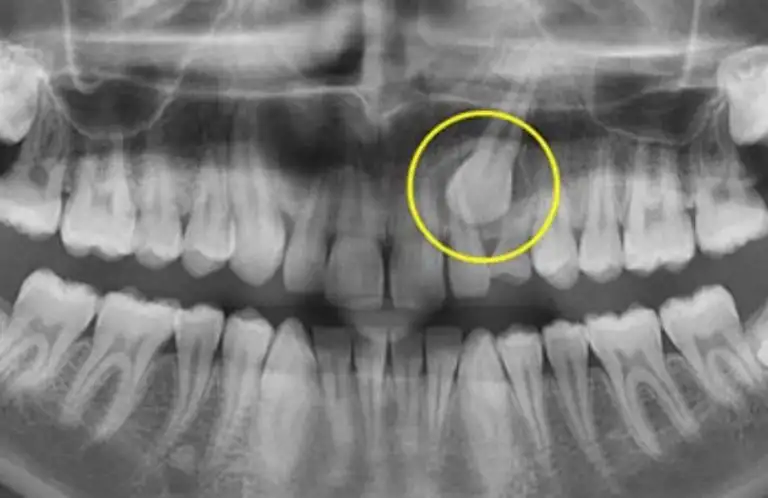

Gömülü diş tedavisi, çene kemiği içinde sürmeyen veya yanlış konumlanan dişlerin ağız sağlığını koruyacak şekilde değerlendirilmesini ve uygun tedavi yöntemlerinin planlanmasını amaçlar; böylece olası ağrı, enfeksiyon ve komşu dişlere zarar verme risklerinin önüne geçilmesi hedeflenir.